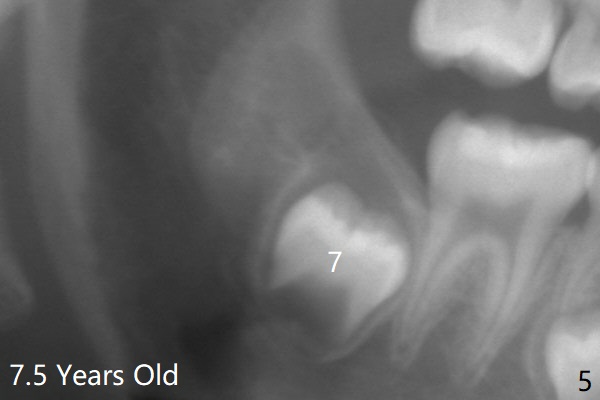

The tooth bud of LL8 appears to be close to that of LL7 at the age of 7.5 years (Fig.5).病人7岁时左下智齿牙胚好像已经接近7(图五与右侧比较)。现在左下七冠方仿佛有牙囊(图十四*)和隧道(T)。拔除智齿时,七牙合面骨质应该去除。术前将拍摄CT。